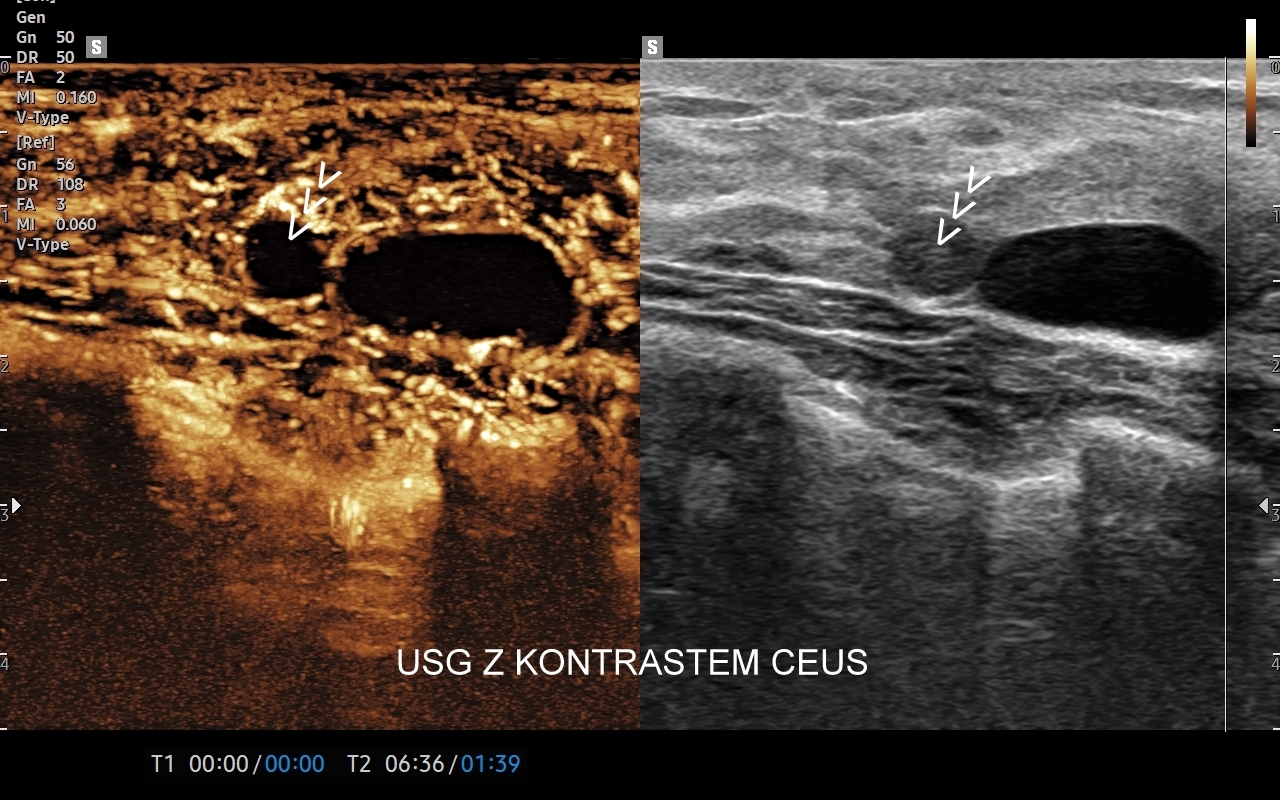

Interdyscyplinarna Pracownia USG we Wrocławiu prowadzona od 2011 r. przez dr Tomasza Szczepańskiego służy Państwu szerokim zakresem badań u Dzieci i u Dorosłych. Wykonać w niej można ponad 40 rodzajów badań USG w ramach diagnostyki podstawowej i specjalistycznej. Korzyścią dla Pacjentów jest również sposobność realizacji kompleksowych badań łączących różne techniki i zakresy, w tym kompleksowego USG szyi, MPUS obszaru brzucha, czy kompleksowego USG kończyn. Pracownia jest wiodącym ośrodkiem wykonującym badania USG z kontrastem CEUS.

• w 2022 r. wprowadził do rutynowego zastosowania w warunkach ambulatoryjnych badania USG z kontrastem (CEUS);

• badania USG z kontrastem (CEUS),

Dr Tomasz Szczepański zajmuje się kompleksową opieką medyczną nad swoimi Pacjentami. W ramach Interdyscyplinarnej Pracowni USG Wrocław wykonuje szereg uzupełniających się badań, zarówno klasycznych, jak USG jamy brzusznej, USG tarczycy, USG piersi, pełen zakres diagnostyki USG Doppler, jak i wysokospecjalistycznych, w tym badania multiparametryczne (MPUS), badania USG z kontrastem (CEUS), ocena przetok dializacyjnych, badania USG Doppler przepływów nerkowych, czy badania USG twarzy